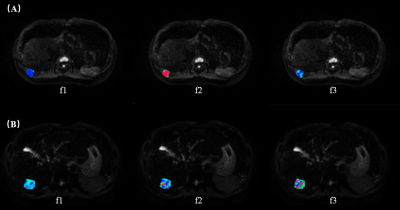

A total of 36 patients with suspected liver tumors who underwent abdominal MRI were included in this study. All the RSI images were acquired using a 3.0T MR scanner (uMR 790, United Imaging Healthcare, Shanghai, China) with 13 b values (b values: 0,25,50,100,150,200,400,600,800,1000,1500,2000,and 3000 s/mm2). Parametric maps were calculated by previously reported fitting methods (Figure 1). The apparent diffusion coefficient (ADC) and the restricted (f1), hindered (f2) and free diffusion (f3) parameters of the three-compartment RSI model were calculated. The intraclass correlation coefficient (ICC) was used to evaluate the consistency of the measured results. Independent sample t-test, Mann-Whitney U test, DeLong test and receiver operating characteristic (ROC) curve analysis were used for statistical evaluation.

Figure.1 Parametric maps derived from the RSI including the f1 map, f2 map and f3 map of a 51-year-old female patient with hepatic hemangioma (A) and a 55-year-old male patient with hepatocellular carcinoma (B) .